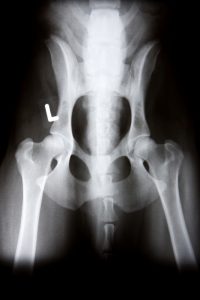

Digital Radiology

At GCVC, we have digital radiology to allow us to obtain diagnostic images of your pet in seconds. We also have the ability to send off your pet’s radiographs to board certified specialists for second opinions in cases that require special treatments.